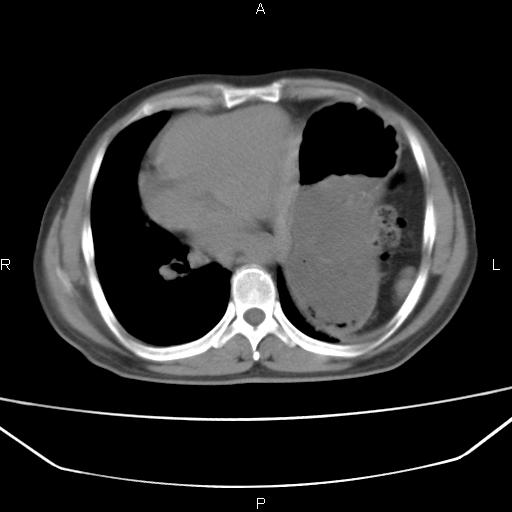

患者,男。50岁。近几日有咳嗽症状,无其他不适,既往病史无,考虑膈疝。请前辈们看看指导指导。

膈膨升,左下肺通气不良,膈肌好像还完整。

考虑左侧膈疝。

左侧膈疝。

符合隔膨升,膈肌较完整。